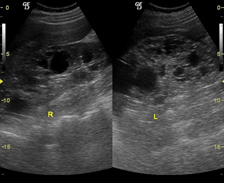

Tüm batın USG,

Alt batın USG,

Üst batın USG,

Üriner USG

CİHAZ; Esaote Mylab25, portable color doppler